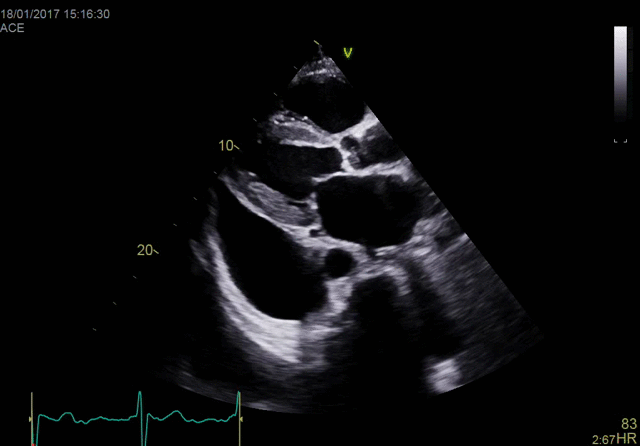

Vivid E95